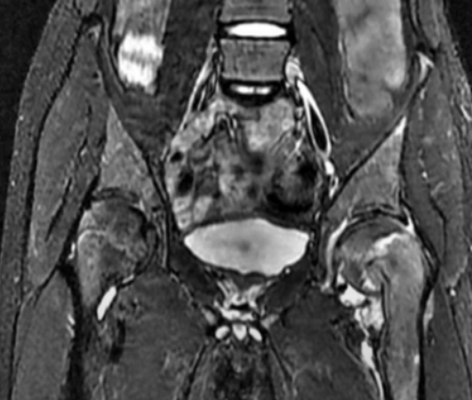

Магнитно-резонансная томография

Метод магнитно-резонансной томографии (МРТ) в настоящее время получает все большее распространение, однако, ввиду своей высокой стоимости, все еще не используется как рутинное исследование. Тем не менее, многие патологические состояния таза могут быть идентифицированы на ранней стадии именно посредством МРТ, т. к. сустав включает большой процент мягких тканей. В настоящее время МРТ активно используется для разрешения спорных случаев: диференциации синовита от септического артрита и остеомиелита, диагностики воспалительных заболеваний сустава, опухолей кости, а также ранней диагностики и контроля болезни Пертеса (остеохондропатия головки бедренной кости) [8, с.8].

В случае ДТБС МРТ может использоваться в тяжелых случаях для уточнения информации перед хирургическим вмешательством, т. к. на МР-томограммах не только воспроизводятся все углы и прочие данные, что видны на рентгенограмме, но и визуализируется сустав в целом: рельеф поверхности головки бедренной кости, внутрисуставные взаимодействия, аномалии хрящевой ткани. Помимо этого, метод МРТ доказал свою непревзойденность в исследовании вертлужной впадины: дифференцировки разрывов губы от других видов повреждений, а также от вариантов нормы [8, с.9-10].